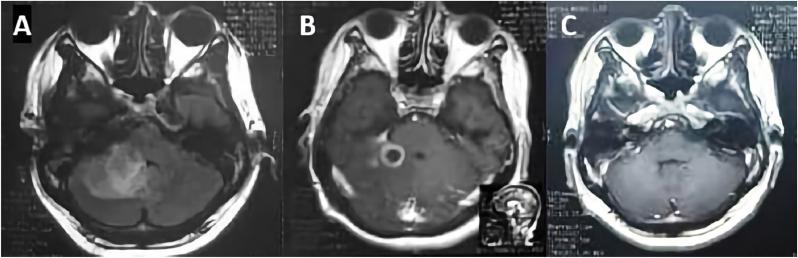

We present two cases of patients with cerebellar abscess. In both cases, patients had the same initial symptoms of fever and central vertigo, with otitis media as the source of infection. However, one patient had generalized onset of tonic-clonic seizure. Both patients were given the same regimen of antibiotics for six weeks and then, evaluated on a clinical and radiological basis via computed tomography (CT) and magnetic resonance imaging (MRI). Sixth weeks after treatment was initiated, No. abscesses were detected in either patient; clinically, there were no complaints or neurological deficits.

我们呈现两例小脑脓肿患者。两例患者最初均有发热和中枢性眩晕症状,感染源均为中耳炎。然而,其中一名患者出现全身性强直阵挛发作。两名患者均接受了为期六周的相同抗生素治疗方案,随后通过计算机断层扫描(CT)和磁共振成像(MRI)进行临床和影像学评估。治疗开始六周后,两名患者均未检测到脓肿;临床上,患者无不适主诉或神经功能缺损。